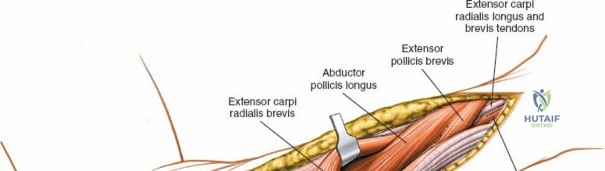

The anterior approach to the radius is an elegant example of utilizing true internervous planes to achieve deep exposure without denervating musculature. Distally, the internervous plane lies between the brachioradialis muscle (innervated by the radial nerve) and the flexor carpi radialis muscle (innervated by the median nerve). Proximally, the plane transitions to lie between the brachioradialis (radial nerve) and the pronator teres muscle (median nerve). Exploiting this plane allows the surgeon to mobilize the entire lateral muscular compartment (the "mobile wad" comprising the brachioradialis, extensor carpi radialis longus, and extensor carpi radialis brevis) away from the anterior flexor compartment.

Superficial Surgical Dissection and Internervous Plane

Incise the deep fascia of the forearm in line with the skin incision. The initial goal is to identify the medial border of the brachioradialis as it courses down the forearm. It is a common pitfall to search for this border too far laterally. At the level of the elbow, the brachioradialis is expansive and extends almost halfway across the anterior forearm. It is surprisingly easy to mistake the plane between the brachioradialis and the extensor carpi radialis longus for the correct intermuscular plane.

To confirm the correct plane, look for the superficial branch of the radial nerve. This sensory nerve runs on the undersurface of the brachioradialis muscle. Once the true medial edge of the brachioradialis is found, develop the plane between it and the pronator teres (proximally) or the flexor carpi radialis (distally). Retract the brachioradialis laterally, taking care to keep the superficial radial nerve attached to its undersurface to protect it from traction injury.